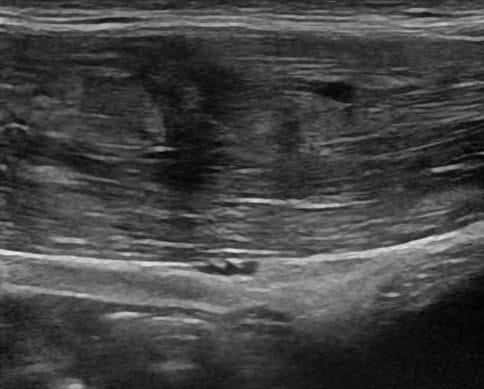

Chấn thương thành bụng

» Thông tin: Nam giới – 18 tuổi.

» Lâm sàng: Chấn thương thành bụng.

# Đụng dập, tụ máu cơ thành bụng.